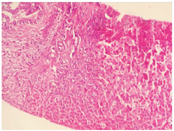

患儿,男,4岁,因"间断腹泻0.5年,皮肤、巩膜黄染5 d"于2017年3月11日就诊于复旦大学附属儿科医院。患儿0.5年前开始反复出现油腻饮食后腹泻,为稀糊便,1~2次/d,无黏液脓血,无发热、腹痛、皮肤黄染,可自行缓解。曾予中成药调理,无明显改善。入院前5 d因体检发现贫血后口服铁剂治疗,渐出现皮肤、巩膜黄染,无发热,不伴腹痛、腹泻及大便颜色变浅,无皮肤瘙痒,无纳差、乏力、恶心、呕吐,小便深黄。发病后曾到当地医院住院治疗2 d,检查发现肝功能异常,贫血、白蛋白低下、凝血功能异常、IgG低下,为进一步诊治,转至复旦大学附属儿科医院。患儿系第1胎,第1产,足月顺产,出生体质量3 650 g,无窒息及抢救史。患儿出生后母乳喂养,按时添加辅食。运动及智力发育与同龄儿相仿;出生后接种卡疫苗后出现左腋下淋巴结脓肿;婴儿期曾2次患重症肺炎并行机械通气。父母体健,非近亲结婚,无明确家族性、遗传性疾病史。体格检查:体质量13 kg,身高95 cm。贫血貌。颈部及腋下可触及黄豆大小淋巴结,皮肤及巩膜中度黄染,无肝掌、蜘蛛痣。心肺查体无特殊,肝脏肋下3 cm,剑突下3 cm,质韧,脾脏肋下未触及。主要实验室检查:血常规白细胞18.4×109/L,嗜酸性粒细胞0.188,血红蛋白84.2 g/L,中性粒细胞0.105,血小板557×109/L,网织红细胞0.064,C反应蛋白64 mg/L;血生化:白蛋白23.9 g/L,碱性磷酸酶171 IU/L,丙氨酸转氨酶132 IU/L,天冬氨酸转氨酶199 IU/L,磷酸肌酸激酶1 710 IU/L,肌酸激酶105 U/L,肌酸激酶同工酶105 IU/L,结合胆红素93.2 μmol/L,γ-谷氨酰转移酶673 IU/L,球蛋白14.7 g/L;钾4.3 mmol/L,乳酸脱氢酶571 IU/L,血氨78 μmol/L;Coomb′s试验阴性;血甲胎蛋白、癌胚抗原、铁蛋白、神经元特异性烯醇化酶均正常;血IgA 0.44 g/L,IgG 2.40 g/L,IgM 0.97 g/L;总IgE 10.0 kU/L;CH50正常,补体C3、C4正常;流式细胞检测CD系列未见明显异常,活化淋巴细胞正常;结核菌T细胞斑点检测(T-SPOT)阴性,血寄生虫抗体阴性,大便常规、隐血及寄生虫检查均未见异常;支气管镜肺泡灌洗液:抗酸杆菌阴性,灌洗液半乳甘露聚糖(GM)试验阴性;腹部磁共振成像(MRI)、磁共振胰胆管成像(MRCP)示肝内胆管、肝总管、胆囊及胆总管扩张(图1);胸部CT示两肺多发斑片、条索状高密度影,局部与邻近胸膜黏连,局部支气管管腔扩张。胸腔见少量积液。骨X线片:双下肢诸骨骨质稀疏(图2);肝脏病理:肝细胞肿胀,部分气球样变,部分肝细胞胞质内见小空泡形成,少量肝细胞内胆汁淤积;部分肝血窦轻度扩张,枯否细胞轻度增生;汇管区纤维组织增生,胆小管增生,部分大胆管周围纤维组织增生,较多嗜酸性粒细胞及少量淋巴细胞、中性粒细胞浸润(图3)。胃镜及小肠胶囊内镜提示浅表性胃炎(轻度),小肠黏膜炎;胃窦黏膜病理活检:轻度慢性炎症,幽门螺杆菌(-)。骨髓涂片未见明显异常。入院后积极给予无脂且蛋白以植物蛋白为主饮食,头孢曲松抗感染,静脉丙种球蛋白、白蛋白、补充脂溶性维生素支持治疗,熊去氧胆酸利胆,患儿腹泻、胆汁淤积好转。获得患儿监护人知情同意后对患儿家系进行高通量测序发现,患儿CD40LG基因突变(exon5 c.506A>G,p.Y169C),169位氨基酸有酪氨酸变为半胱氨酸,为致病性突变(rs786205606),母亲为携带者,为已知X连锁隐性遗传性疾病致病性基因突变。